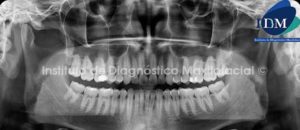

Paciente de sexo masculino de 21 años de edad acude a la consulta radiológica para la evaluación preoperatoria a la extracción de las terceros molares inferiores.